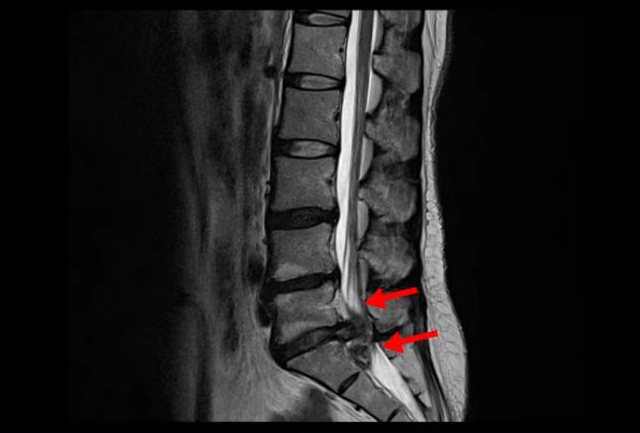

<5-1번 디스크 파열>

이 환자분의 허리 MRI를 보면 5번, 1번 디스크가 매우 심하게 터져 있는 것이 보입니다. 굉장히 심한 허리디스크터짐으로 인해 신경이 있어야 할 곳을 밀려나온 디스크 수핵이 거의 다 차지하고 있는 것을 볼 수 있습니다.

디스크가 심하게 터져서 수핵이 많이 밀려 나오니까 수핵이 위로도 밀려 올라가고 아래로도 흘러내려 있습니다.

축상면으로 보면 수핵이 위로도 밀려 올라가서 신경 공간을 까맣게 차지하고 있는 것이 보입니다.

아래로도 저 밑에까지 흘러내려가 신경 공간을 많이 차지하고 있어서 신경의 형태가 제대로 보이지가 않습니다.

MRI로 이 정도의 심한 파열이 보이면 다리에 마비나 대소변 장애까지도 있지 않을까 의심될 수 있는 상황인데요. 그래서 환자분이 MRI를 찍은 정형외과에서도 대소변 장애는 없는지 확인하였고, 파열이 심하니까 무조건 바로 수술을 해야 한다고 얘기했다고 합니다. 그런데 다행히도 이 환자분은 다리에 감각 마비와 보행 시 힘 빠짐 증상은 있으나, 대소변 장애는 없었습니다.